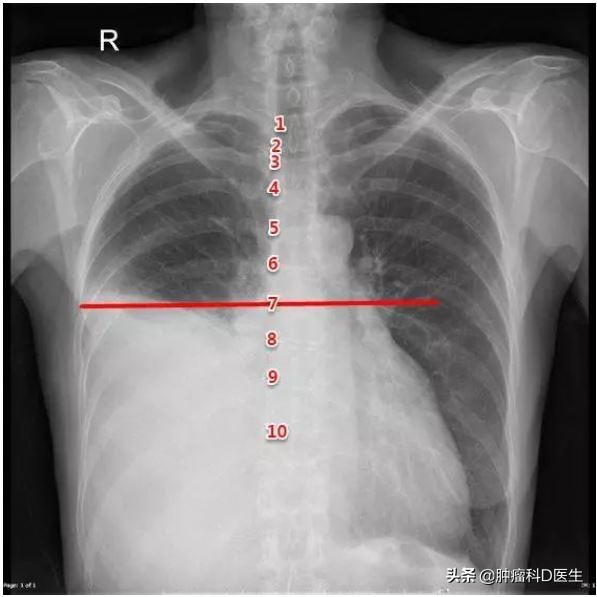

胸部X线下的胸腔积液

影响肿瘤分期:根据肿瘤TNM分期,出现恶性胸腔积液的患者诊断为M1,也就是常说的IV期肺癌;有人说我把胸水抽干净了,是不是就不是IV期了哪?本质上,出现胸水意味着胸膜出现了播散转移,胸膜上的小结节不会跟着胸水被放出来,所以仍然要诊断IV期肺癌。随后的治疗根据IV期肺癌的标准进行。